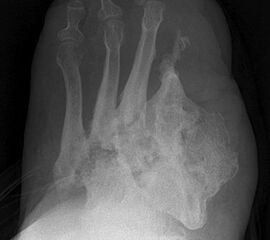

• Lokale Osteomyelitiden mit Knochennekrose und Weichteilbeteiligung (Abb. 50).

Das Ausmaß der Knochenresektion ergibt sich aus der Defektgröße bzw. aus der Ausdehnung der Osteomyelitis 3 (Abb. 52). Eine totale Kalkanektomie ist problematisch, weil danach die Leitungsbahnen unmittelbar dem Körpergewicht ausgesetzt sind.